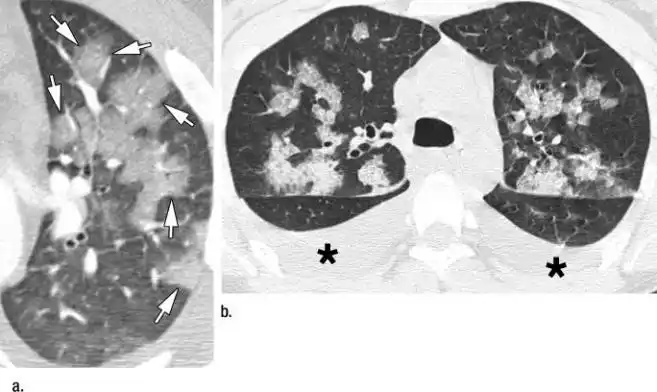

全小叶密度增高-磨玻璃影:(a)hrct 显示小叶性肺炎(支气管肺炎),左肺